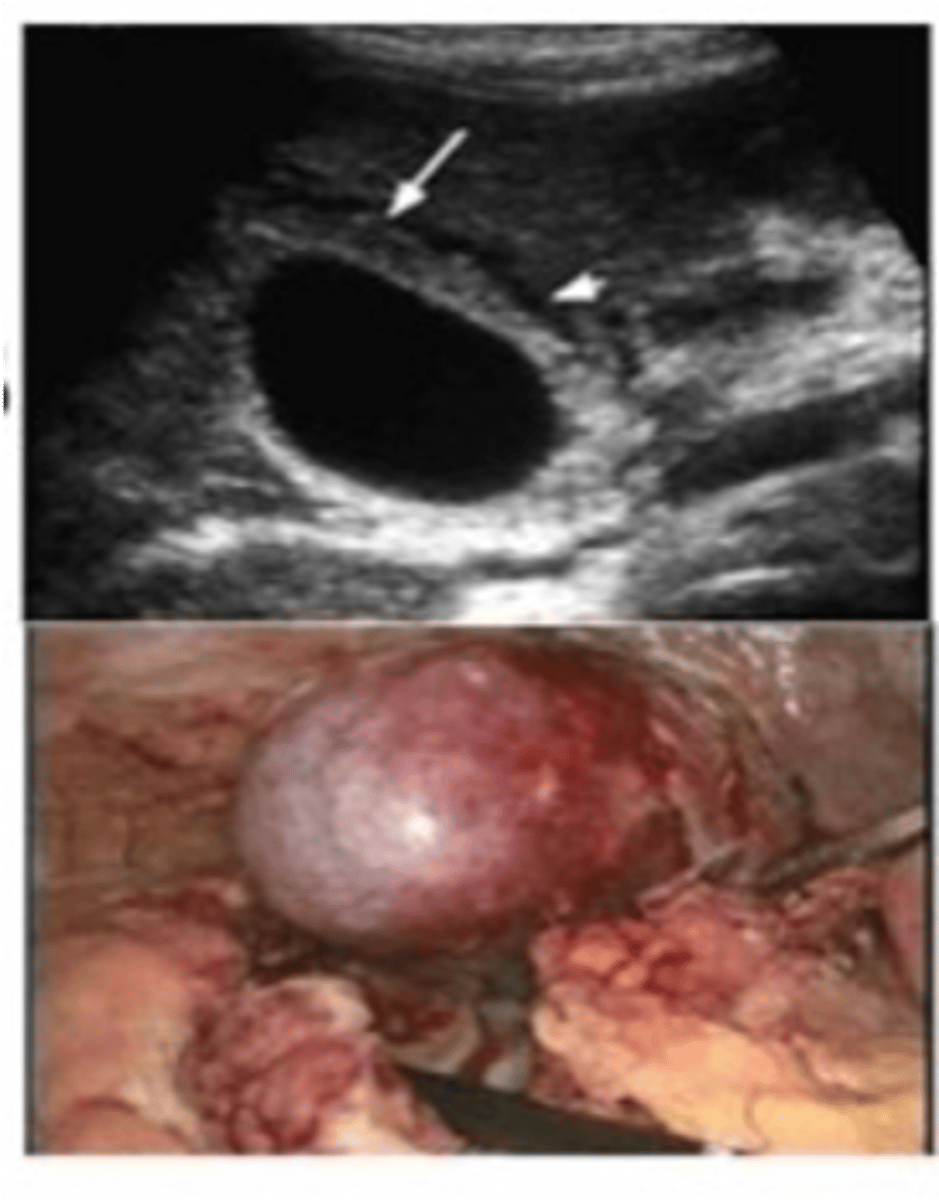

Pancreatic Pseudocyst

Define Condition:

Encapsulated collection of fluid formed by fibrous/granulation tissue surrounding liquefactive necrosis and pancreatic enzymes (no epithelial lining of cyst)

-Hx: Weeks after episode of Acute Pancreatitis

-Prog: Usually resolves spontaneously but may be infected & ruptured --> release of enzymes into abdominal cavity